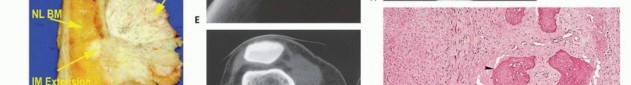

Tumor Growth Dynamics and the Pseudocapsule

Unlike carcinomas, which grow via direct infiltrative destruction, sarcomas typically form a solid, cohesive mass that expands centrifugally. The periphery of the lesion is the most biologically active and least mature zone.

Benign lesions are often constrained by a true capsule composed of compressed, mature normal cells. In stark contrast, sarcomas are enveloped by a "pseudocapsule." This reactive zone consists of compressed malignant cells, a fibrovascular stroma, and a dense inflammatory infiltrate interacting with the surrounding host tissue. The pseudocapsule is highly deceptive; it is not a true anatomic barrier but rather a tumor-host interface.

The thickness and integrity of this reactive zone vary with tumor grade. High-grade sarcomas feature a poorly defined, highly permeable reactive zone that is frequently invaded by microscopic tumor extensions.

* Satellite Lesions: Microscopic or macroscopic tumor foci located within the reactive zone/pseudocapsule.

* Skip Metastases: Tumor nodules that have broken through the pseudocapsule and reside outside the reactive zone but remain within the same anatomic compartment. These represent locoregional micrometastases that have spread via local tissue planes or marrow sinusoids, independent of systemic circulation. The presence of skip metastases (seen in <5% of osteosarcomas preoperatively) is a dire prognostic sign and accounts for local recurrences when seemingly adequate margins are achieved without recognizing the skip lesion. Low-grade sarcomas may interdigitate into the reactive zone but rarely form true skip metastases.

Anatomic Barriers and Compartmentalization

Sarcomas generally respect major anatomic boundaries, taking the path of least mechanical resistance. They initially expand within the specific anatomic compartment of origin (e.g., the anterior compartment of the thigh, or the medullary canal of a bone). Only in advanced stages, or following iatrogenic violation (e.g., a poorly planned biopsy), do they breach the compartment walls—such as thick muscular aponeuroses, fascia, or cortical bone—to invade adjacent compartments.

Tumors are defined surgically as intracompartmental if they are entirely contained within their native anatomic compartment. They are extracompartmental if they have breached a fascial/cortical barrier, or if they originate in an uncompartmentalized space (e.g., the popliteal fossa, axilla, groin, or antecubital fossa). Most high-grade primary bone sarcomas are bicompartmental at presentation, having destroyed the native cortex via the Haversian and Volkmann canals to form a contiguous soft tissue mass. Carcinomas metastatic to the extremity, unlike primary sarcomas, ignore compartmental boundaries and exhibit true infiltrative growth.